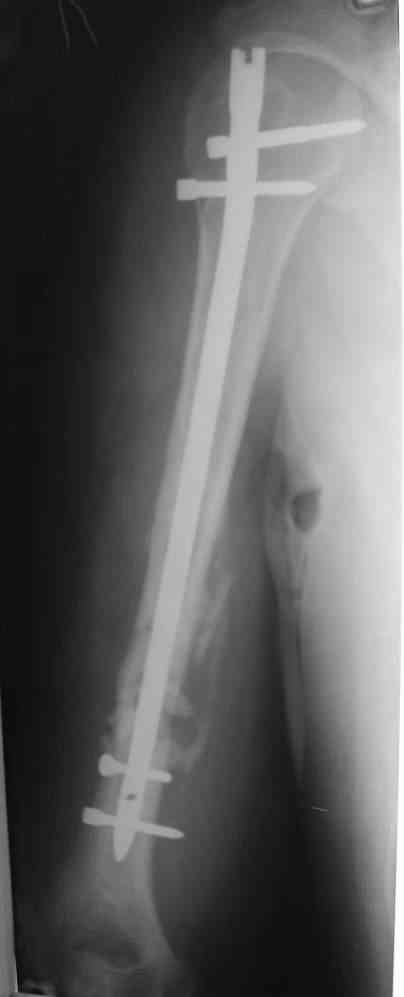

На мой взгляд, целесообразно выполнить антеградный блокируемый интрамедуллярный остеосинтез. При наличии достаточного диаметра костномозгового канала по проводнику произвести его рассверливание и установить штифт по-возможности без вскрытия места перелома. При наличии симптомов повреждения лучевого нерва необходимо выполнить его ревизию и мобилизовать отломки "открыто".

Предложение коллеги Мамонова, возможно, более привлекательно. У пациентов с невысокими функциональными потребностями есть смысл добиваться не сращения, а стабильной, безболезненной и функциональной конечности, что может быть достигнуто "эндопротезированием диафиза" интрамедуллярным стержнем. У нас несколько таких больных наблюдаются уже 2-3 года, вроде неплохо.

Будут трудности с закрытым вскрытием канала (нужен инструмент типа длинного шила). Можно взять штифт с блокированием, а можно и прямоуголного сечения типа Зверева-Ключевского. Есть варианты закрытого штифтования в нейтральном положении, с компрессией, открыто с резекцией и компрессией.

Мы бы предложили БИОС ретроградно (хотя это не принципиально, можно и сверху). Учитывая,что ложняк "болтающияся", больших трудностей с закрытым вскрытием канала (в зоне ложного сустава) быть не должно. Конечно нужен инструмент: сначала длинная (350-400 мм) острая спица (шило)диаметром 4-5 мм., затем гибкие развертки до 8-9 мм и соответствующий массивный штифт...

Штифт - отвисание проксимального отдела - накостный остеосинтез, нагноение, АФВ с ревизиями раны, опять пластина и снова нестабильность. Была удалена пластина и выполнен БИОС штифтом ChM (ДЕОСТ). Через 2 нед. пациент сел за руль и вышел на работу. Причем так и работает до сих пор уже 1,5 года, хотя полного сращения мы вроде бы не достигли ( снимки пришлю позже) - пациент не приходил на осмотры, общался только по телефону.